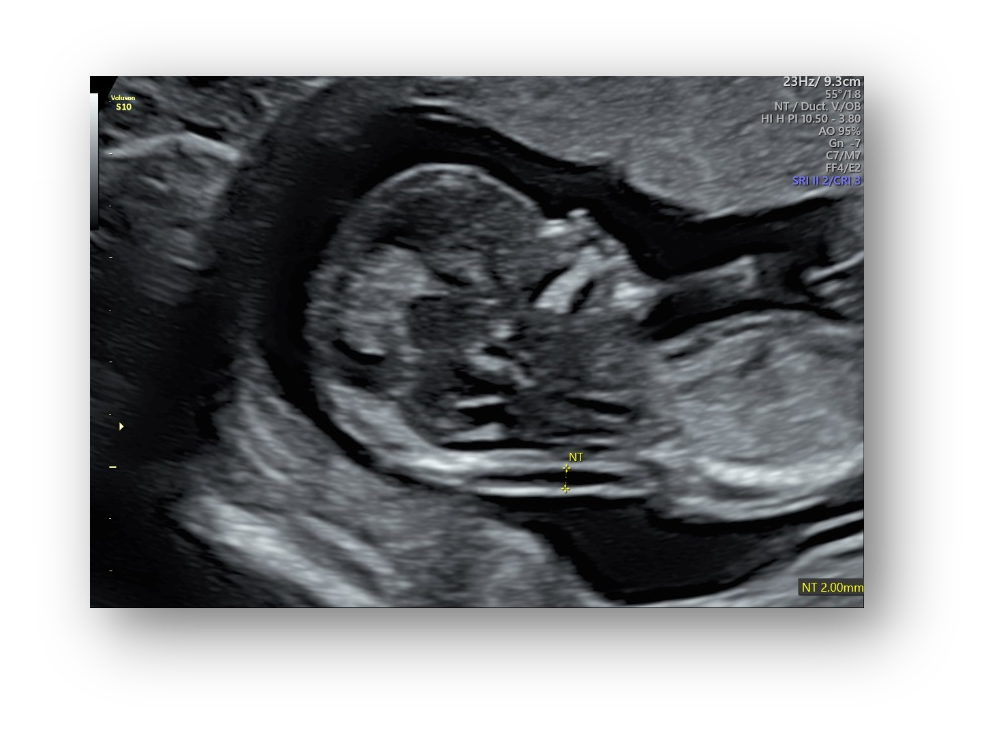

SonoCNS

自动识别4个标准切面:

正中矢状面,经丘脑平面,经小脑平面,经侧脑室平面

自动测量6组生物指标:

BPD 双顶径,HC 头围,CM 后颅窝池,Cereb. 小脑横径,Vp 侧脑室后脚,OFD 枕额径